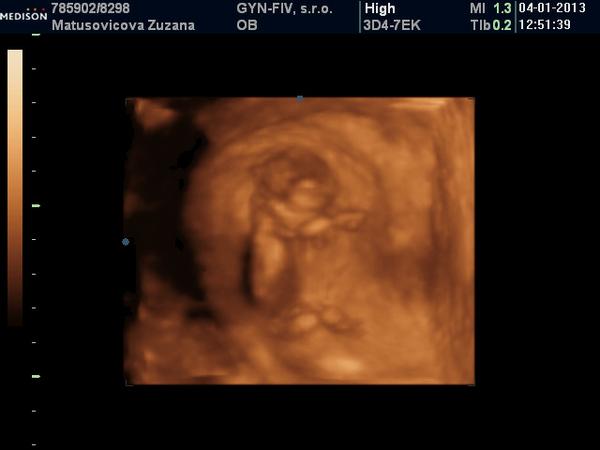

A na gynekológii všetko v poriadku. Bábo má 6,2cm. Som presne 13+0tt. NT nameral 2,2 /na 3D v piatok to bolo 1,5/. Vraj to vyzerá na chlapca, ale to mi napísal s otáznikom. Bol so mnou aj manžel aj Viki a keď vošli dnu, bábo akurát zakývalo, tak sme sa vytešovali 😉. Ale mala som vyšší tlak-140/95. Mám si dávať Magnézium ráno a večer, 3x za deň merať tlak a v piatok tam mám zavolať, že čo a ako. Ak nič, tak v pohode a ak bude vyšší, budeme to potom riešiť.